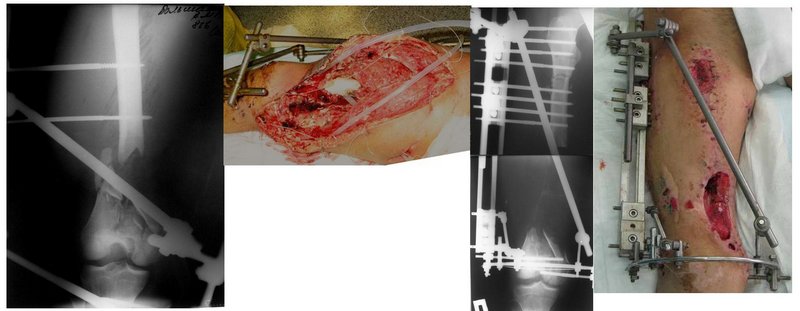

Если у Вас возникнут какие-то сомнения, то возможно наложение гибридного циркулярного-монолатерального дистракционного аппарата на левое бедро и выполнение остеотомии в в/3 бедра. Почему монолатеральный гибридный аппарат, а не аппарат Илизарова? Эта конструкция гораздо легче переносится пациентами, в ней гораздо удобнее проводить местное лечение ран.

Разрешите рассказать о пациенте, которому мы фиксировали перелом такой конструкцией.

Больной 19 ти лет, пострадал в результате ДТП, пассажир мотоцикла. Получил открытый оскольчатый перелом н/3 левой бедренной кости 3a тип по Гастилло-Андерсену. При поступлении ПХО ран, фиксация стержневым аппаратом наружной фиксации. Лечение больного осложнилось развитием анаэробной флегмоны левого бедра. Лампасные разрезы, неоднократные некрэктомии, некротизировался участок диафиза левой бедренной кости на протяжении 15 см. Произведена резекция. 20.05.10- демонтаж АНФ, остеоситез левой бедренной кости гибридным циркулярно-монолатеральным стержневым дистракционным аппаратом наружной фиксации, остетомия левой бедренной кости в в/3. Сейчас начата дистракция в аппарате, проводится подготовка ран к аутодермопастике.

С уважением. Удачи!

5.jpg